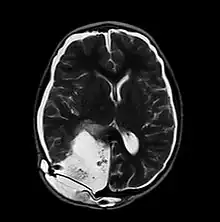

MRI of Pseudomeningocele in 8 years old male patient

A pseudomeningocele is an abnormal collection of cerebrospinal fluid (CSF) that communicates with the CSF space around the brain or spinal cord. In contrast to a meningocele, in which the fluid is surrounded and confined by dura mater, in a pseudomeningocele, the fluid has no surrounding membrane, but is contained in a cavity within the soft tissues.